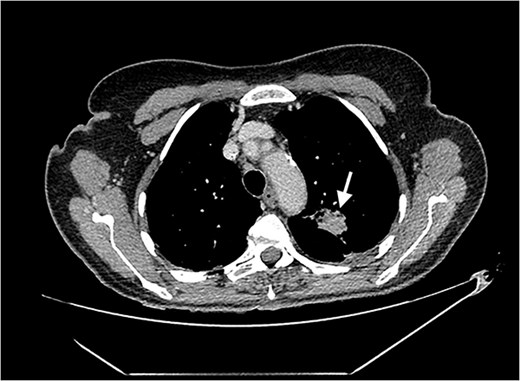

Echocardiography revealed a 1.2 cm pedunculated mass attached to the anterior mitral valve leaflet (AMVL) with severe mitral regurgitation (Fig. 1). Computed tomography imaging revealed multiple hepatic lesions (suspected septic emboli, Fig. 2), and a cavitating mass in the posterior aspect of the left upper lobe of the lung (Figs 3 and 4). Magnetic resonance imaging showed multiple cerebral lesions (Fig. 5), also thought to be septic emboli. Her presentation was suspected to be due to infective endocarditis rather than ischaemic, as troponin was negative, and coronary angiography was unremarkable. She was therefore treated promptly with intravenous vancomycin and gentamicin as per local antimicrobial guidelines. However, she failed to recover, and her case was reviewed in the regional in-house urgent cardiac surgical multidisciplinary team meeting. Considering her persistent fever, as well as the recurrent emboli, the decision was made to transfer her to our centre for emergency surgery.

Coronal CT image of the lungs showing the cavitating mass suspected to be an abscess.